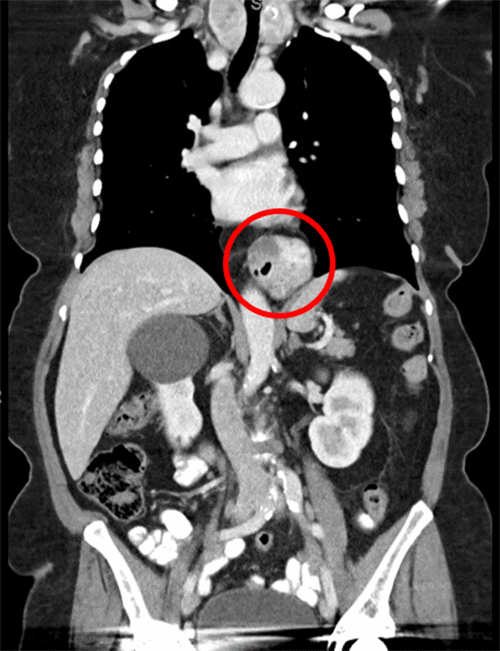

Figure 3. Hiatal Hernia Apparent in CT Scan. Published with Permission

The patient was subsequently referred to a general surgeon to address the tumor and hiatal hernia. The CT was reviewed, and a subsequent upper GI swallow study (Figure 4) was ordered. The UGI swallow study was conducted to evaluate the esophagogastric anatomy and functionality. The patient was determined to be a good surgical candidate for a robotic gastric wedge resection. Additionally, a hiatal hernia repair was planned to occur at the time of the tumor removal. There would be no neoadjuvant therapy ahead of the procedure.